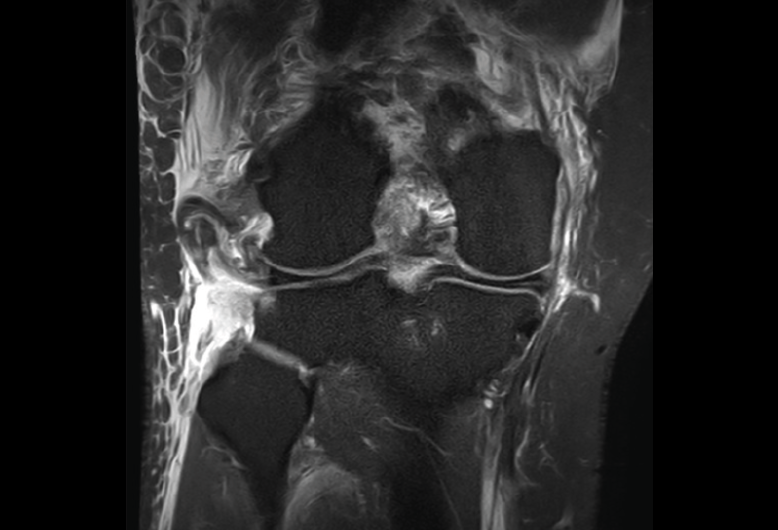

Numerosos estudios demuestran la utilidad de la RM para definir la estabilidad o inestabilidad de la lesión en la osteocondritis, destacando su carácter no invasivo y la capacidad de valorar la progresión y la respuesta al tratamiento(21)(Figuras 53 y 54).

Figura 54. Corte de secuencia T1 y T2 Fat-Sat coronal de resonancia magnética: gran osteocondritis en el cóndilo femoral interno con edema en la medular adyacente.